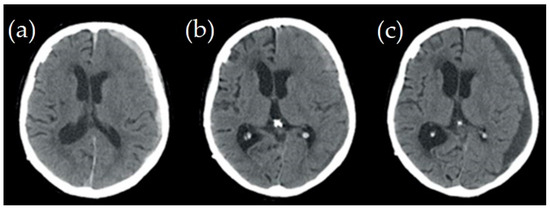

| Brain Parameters (White and Grey Matter) | Young Adults (28 y) ![]() | Senior (77 y)![]() | Difference (Young Adult vs. Senior) | Comments |

| Brain Volume | 1.0406 [dm3] | 0.98088 [dm3] | 5.7% | Young Adults: On average, young adults tend to have larger brain volumes compared to older adults, with a ~6% difference. This is largely due to ongoing brain development and growth during childhood and adolescence [40]. Senior Adults: Brain volume typically decreases with age. This reduction can be attributed to factors such as loss of neurons and their connections, as well as changes in brain structural integrity. This decrease in volume can affect various cognitive functions. |

| Brain Area | 165,893.3 [mm3] | 1,619,62.1 [mm2] | 2.4% | Young Adults: Younger individuals generally have a larger brain area compared to older adults, with a ~2% difference. The brain area encompasses the surface of the brain, which is important for processing information and facilitating communication between different brain regions. Senior Adults: Over time, there may be a slight reduction in the brain’s surface area. This could be related to the gradual decline in cognitive functions, such as memory and processing speed, experienced by some older individuals. |

| Brain Mass | 1.18 [kg] | 1.02 [kg] | 13.3% | Young Adults: Young adults typically have greater brain mass compared to older adults, with a ~13% difference. Brain mass is closely related to brain volume and is largely responsible for the organ’s overall functionality. Senior Adults: As individuals age, there is often a decline in brain mass, primarily due to a decrease in the number of neurons and synaptic connections. This mass reduction can contribute to age-related cognitive decline. |